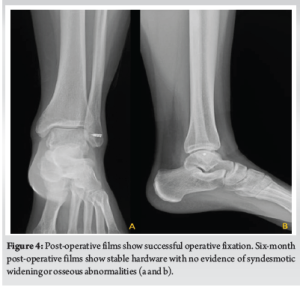

The joint was then thoroughly examined, irrigated, and debrided. There were no osseous or chondral injuries. The ruptured ligaments with the ankle capsule were then approximated and repaired with a heavy non-absorbable suture. Augmentation of the repair was performed with a suture anchor placed in the lateral aspect of the distal fibula. One limb of the anchor was started posteriorly and run along the distal and anterior aspect of the traumatic arthrotomy to reinforce the repair. The other suture was used to further reinforce the repair (Fig. 3). Repeat stress examination of the ankle now demonstrated no residual instability with varus tilt or anterior drawer tests. The wound was closed in a standard layered fashion. A soft sterile dressing and a posterior splint were then applied. She was instructed to remain non-weight-bearing following surgery.